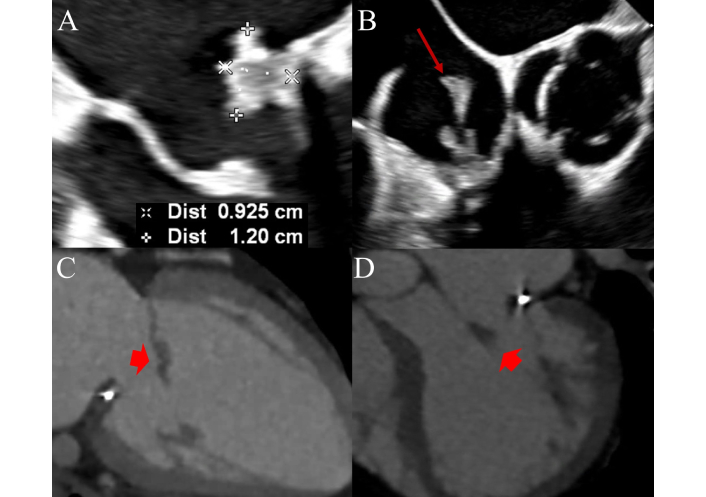

CCT is an increasingly valuable adjunct in IE diagnosis, particularly in the evaluation of PVE and perivalvular extension. It is recommended by the ACC and AHA when echocardiography is limited or equivocal and is especially helpful for assessing aortic valve IE and preoperative planning in prosthetic valve cases [2]. CCT surpasses echocardiography in identifying perivalvular complications such as abscesses, pseudoaneurysms, and prosthetic valve dehiscence. It is less hindered by artifacts from prosthetic material [50–52]. Indications for CCT include: suspected abscess or pseudoaneurysm, PVE, equivocal TEE results, and preoperative coronary artery assessment [53, 54]. CCT can identify vegetations (especially large), abscesses, leaflet perforations, pseudoaneurysms, and valve dehiscence [50, 53, 55]. Sensitivity of CCT for vegetations ranges from 72–97%, with specificity from 84–97%, though it is less effective for small vegetations and leaflet perforation. However, CCT excels in identifying perivalvular complications, with sensitivity for abscess detection approaching 100% [51, 55]. Advantages include high spatial resolution, multiplanar visualization, and comprehensive anatomical assessment, but limitations include radiation exposure, contrast use, and lower sensitivity for small vegetations [51, 52, 55]. CCT aids diagnosis, risk stratification, and surgical planning—especially when high-risk features like large vegetations or abscesses are present, or when coronary artery disease must be excluded prior to surgery [53, 54]. The Society of Cardiovascular Computed Tomography, the ACC, and other societies also highlight the role of CT in delineating extracardiac manifestations of endocarditis, including septic emboli and mycotic aneurysms [56].

Multimodal imaging in PVE, including TEE and CCT, is shown in Figure 4. A comparative summary of key imaging features and diagnostic performance between echocardiography and CT is provided in Table 3.

Mitral prosthetic valve endocarditis on transesophageal echocardiography (TEE) and cardiac computed tomography (CT). Figure 4 shows a case of prosthetic valve endocarditis in a 45-year-old male with prior history of mitral annuloplasty repair. Panel A: TEE showing a four-chamber view showing a large vegetation attached to the posterior mitral leaflet. Panel B: Large mobile vegetation attached to the tricuspid valve noted as well, indicating poly-valvular involvement; aortic and pulmonary valves were not affected (not shown). Arrow pointing to the vegetation. Panels C and D represent cardiac CT imaging performed in preparation for mitral and tricuspid valve replacement. Arrowheads show the anterior mitral leaflet (AML) vegetation appearing as a low-attenuation, soft-tissue mass.